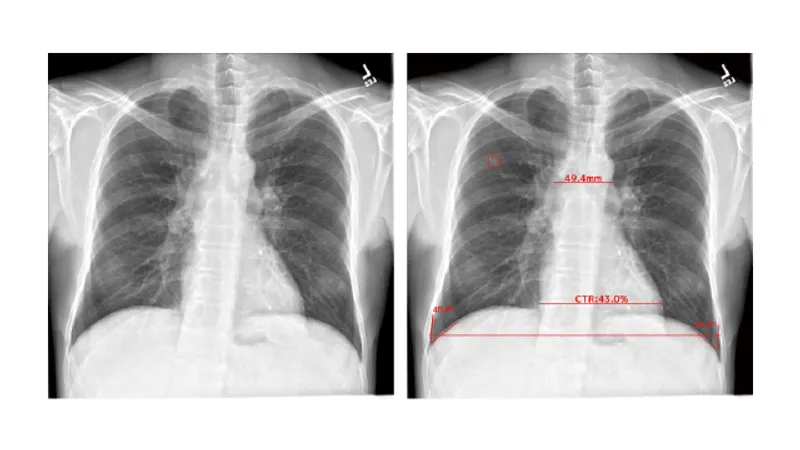

EIRL Chest Nodule: ・胸部X線画像から条件を満たす肺結節の形状に類似した領域(5mm〜30mmまで)[1]を検出し、医師による読影をサポートします。 ・過去に撮影された同一被験者の画像と比較し、肺結節候補域の経時的変化(増減)を表示します。 [1]浸潤性でないもの、胸部内で他臓器との重なりがない候補域に限る。 EIRL Chest Metry: 胸部X線画像の画像情報から、画像に基づく画素値の閾値処理を用いて以下(1)~(5)を計測・算出及び(6)を出力します。 (1)胸腔内の空気含有面積 (2)心胸郭比 (3)縦隔幅 (4)大動脈弓の径 (5)肋骨横隔膜角 (6)過去比較